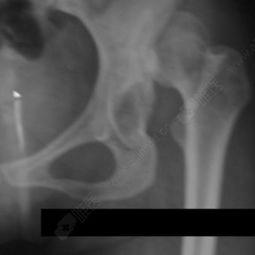

在手术之前,医生会先进行详细的检查,包括X光、CT等,以确定脱臼的具体情况。同时,医生还会根据患者的具体情况制定手术方案。

成人手腕脱臼手术通常采用局部麻醉,患者意识清醒。以下是手术过程的详细描述: